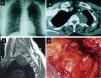

A previously healthy 39-year-old woman was hospitalized for a 3-month history of brachial neuralgia (BN) in the left arm. Physical examination was normal. Left laterotracheal opacity was detected on chest X-ray (Fig. 1A). A well-defined tumor in the left paravertebral region, 6cm in diameter, with some areas of intravenous contrast medium uptake was found on chest computed tomography (CT) (Fig. 1B) and magnetic resonance imaging (MRI) (Fig. 1C). The mass was not compressing the spinal cord and there was no direct invasion of the vertebrae. Laboratory test results and bronchoscopy were completely normal. The apical mass and part of the sympathetic chain were extracted via a left posterolateral thoracotomy (Fig. 1D). The mass showed strong adhesions to the brachial plexus and the stellate ganglion, with widening of the intervertebral space. The pathology report confirmed the diagnosis of ganglioneuroma, in view of the mature ganglion cells contained in a stroma of collagen fibers with the presence of some Schwann cells. In the post-surgical period, the patient presented transient Claude Bernard–Horner syndrome that resolved fully after 2 months. Clinical examination and CT at 3 and 6 months of follow-up were favorable.

(A) Chest X-ray showing left paratracheal opacity. (B) Chest computed tomography showing an encapsulated mass in the left posterosuperior mediastinum at the T2–T3 level. (C) Chest magnetic resonance image: well-defined tumor in the left paravertebral region with no compression of the spinal cord and no direct vertebral invasion. (D) Direct image of ganglioneuroma during surgery. R1: first rib; SG: stellate ganglion; L: lung; BP: brachial plexus; T: tumor.